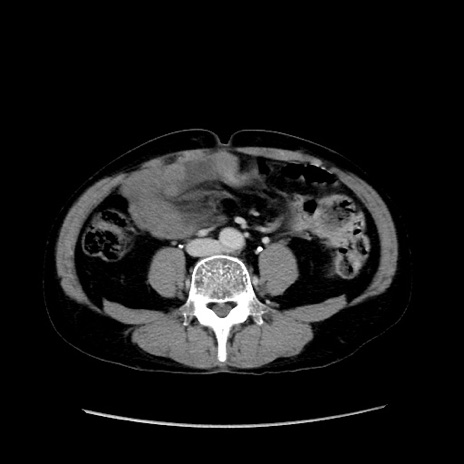

症例37(横断像)

【症例】40歳代 男性

【主訴】腹痛

【現病歴】4時間ほど前に電車に乗車中に臍部上より腹痛出現。徐々に増悪し起立困難となり、救急外来受診。生ものは数日食べていない。今朝お雑煮を食べた。

【身体所見】BT 36.8℃、BP 117/84mmHg、HR 91/min、SpO2 97%、苦悶様、腹部:臍上部広範囲圧痛あり、反跳痛±

【データ】WBC 8100、CRP 0.03